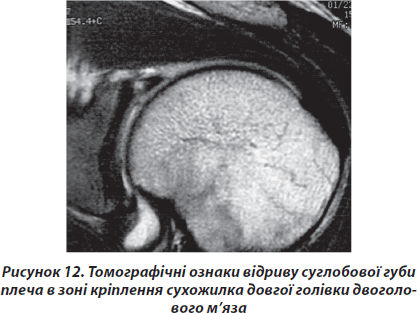

Стандартна магнітно-резонансна томографія виконувалась на апаратах із силою магнітного поля 1 Тесла в сагітальній, коронарній та фронтальній проекціях. Характерною діагностичною ознакою в даному випадку вважали ознаки сепарації між лопаткою та суглобовою губою на фронтальних перерізах (рис. 12).